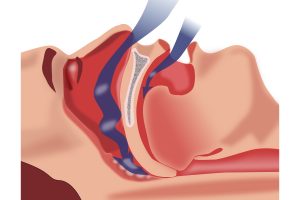

Obstrüktif yani tıkayıcı uyku apnesi türünde hastanın boğaz ve çevresindeki yumuşak dokular hava yollarının tıkarken; merkezi uyku apnesinde hava yolu tıkanmaz ancak beyin solunum sistemine sinyal iletimini başaramaz.

Her yaştan kişide görülebilen uyku apnesi sendromunun temel nedeni boğaz kaslarının solunum yolunu tıkayacak denli gevşemesi olarak belirtilebilir.

Hasta risk faktörlerini ortadan kaldırdığı takdirde uyku apnesi şikayetlerinden kurtulamıyorsa CPAP maskesi ve Ekspirasyonel Pozitif Hava Yolu Basıncı (EPAP) cihazını kullanarak sağlıklı solunum yapabilir.

Uyku apnesine neden olan temel sebep ağız içi anatomisindeki bozukluklar ile ilgiliyse uyku sırasında hava yolunu açık tutmak üzere üretilen özel ağız aparatlarından da yararlanılabilir.